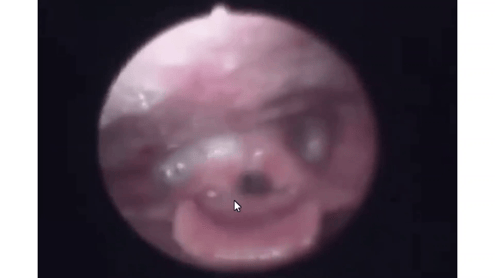

普段食道は閉じているので、唾液は食道に入りません

口からでた唾液は、ダラダラと喉に流れ込む。

喉に入った唾液は、重力によって

肺の入口に向かう。

嚥下反射が起これば、飲み込めるが

嚥下反射が起こらなければ

肺の入口付近に3~5㏄溜まる

溜まる量を超えると肺の入口に向かう。

肺に入れないように防御反応として、むせが起こる。

むせは、肺の中の空気を一気に吐き出し肺の入り口に溜まっている唾液を吹き飛ばします。

唾液が肺の入口を塞ぎ呼吸がしにくい